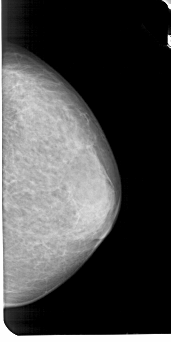

A_1947_1.RIGHT_MLO

RIGHT_CC LINES 5116 PIXELS_PER_LINE 2551 BITS_PER_PIXEL 12 RESOLUTION 43.5 NON_OVERLAY